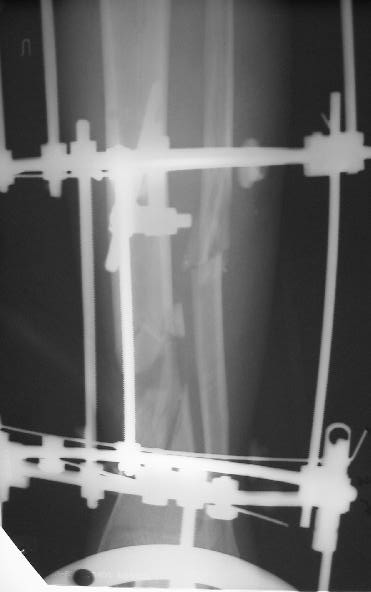

Больного прооперировал, обработку мягких тканей на голени не стал делать, думаю, некроз по краю швов на голени заживет под струпом (рис 3). На стопе удалил некротические ткани, готовлю ее к аутопластике (рис 2).

На дополнительных снимках итраоперационно видна значительная потеря массы (рис 6 рис 1). Хотя на снимках контрольных после операции вроде дефекта значительного нет. Все же придется, как-то замещать дефект костный на голени, думаю подготовить морально больного к повторной операции костной пластике, после заживления ран.

1. Дождаться заживления ран и через 2-3 месяца после заживления провести свободную костную аутотрансплантацию.

2. Провести остеотомию сегментарную м/берцовой кости напротив дефекта и медленно этот сегмент подвести с помощью спиц в место дефекта. Можно не дожидаться полного заживления ран.